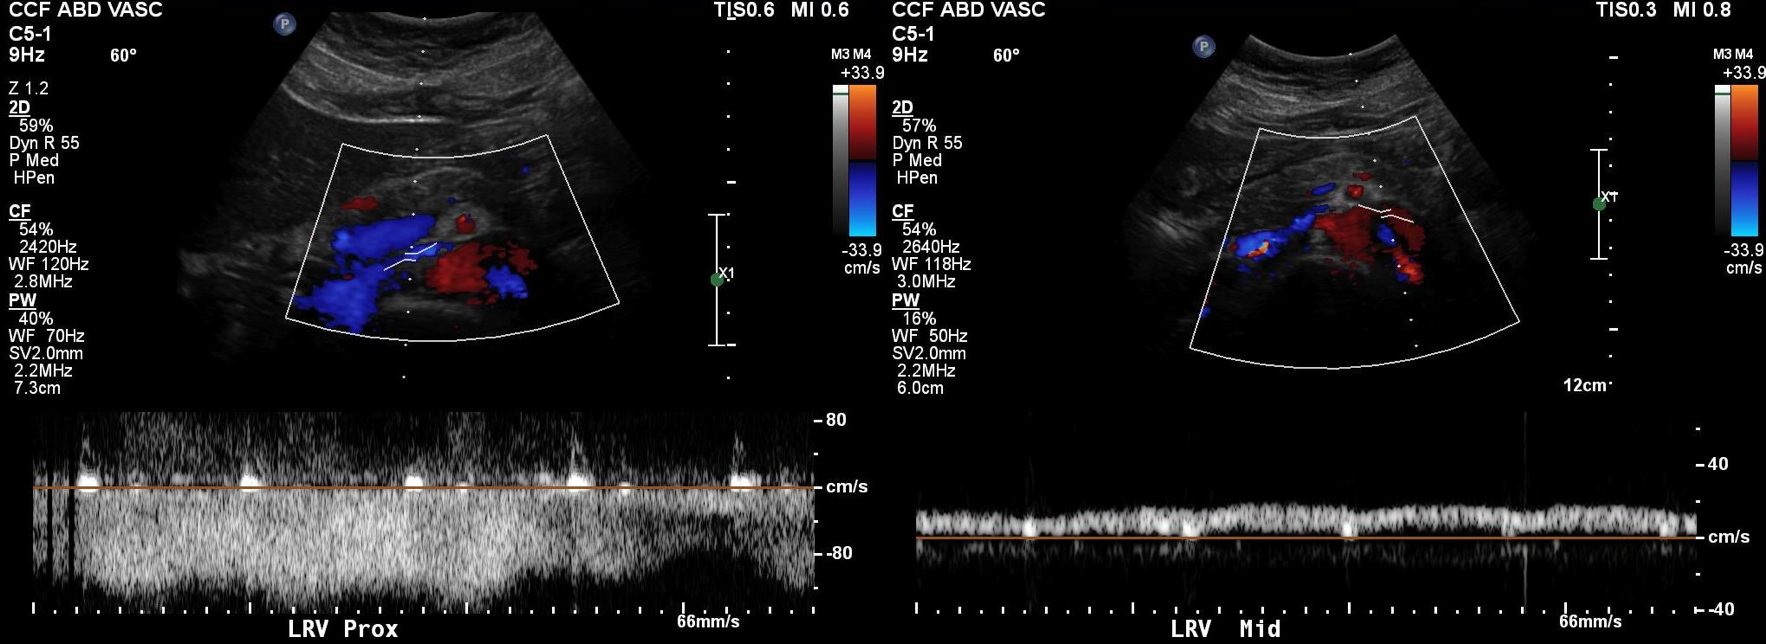

Duplex showed the narrowing in the left renal vein and spectral Doppler showed elevated velocities across the compression caused by the superior mesenteric artery (below). The collecting system was not obstructed.

venous duplex14.jpg

PREOP DUPLEX DOPPLER.png

On the duplex, the proximal left renal vein (LRV) was not visualized. The right kidney had normal parenchymal appearance and blood flows, while the left, the kidney appeared distended and had flows consistent with outflow obstruction.

spectral kidneys

Spectral Doppler flows show respirophasicity in right renal vein(RRV), outflow obstruction on left renal vein (LRV)